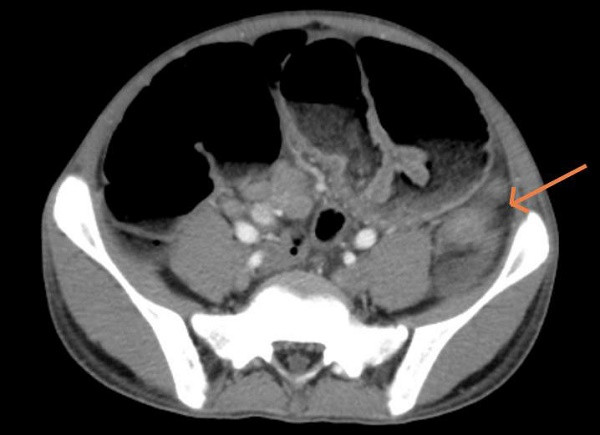

| Hình ảnh cắt lớp vi tính ổ bụng của bệnh nhân. |